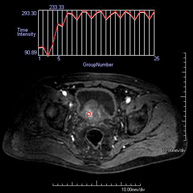

Prueba diagnóstica no invasiva que consiste en la obtención de imágenes de alta definición anatómica de la pelvis mediante el empleo de un campo electromagnético y ondas de radio (con un emisor y un receptor). No utiliza radiación ionizante. Se realiza para estudiar patologías del útero, del ovario, de las trompas y la vagina, ya sean de origen tumoral, inflamatorio o vasculares. Además permite valorar les estructuras adyacentes localizadas en la pelvis, identificando sus alteraciones. A veces requiere el uso de contraste intravenoso (Gadolinio) para caracterizar las lesiones. - RM Pelvis masculina

Prueba diagnóstica no invasiva que consiste en la obtención de imágenes de alta definición anatómica de la pelvis masculina mediante el empleo de un campo electromagnético y ondas de radio (con un emisor y un receptor). No utiliza radiación ionizante. No requiere de preparación previa. En algunas ocasiones requiere el empleo de contraste paramagnético (Gadolinio) para caracterizar las lesiones. Esta prueba permite valorar órganos como la vejiga urinaria, la unión entre los uréteres y la vejiga, la próstata, las vesículas seminales, la uretra, los huesos de la pelvis, etc.